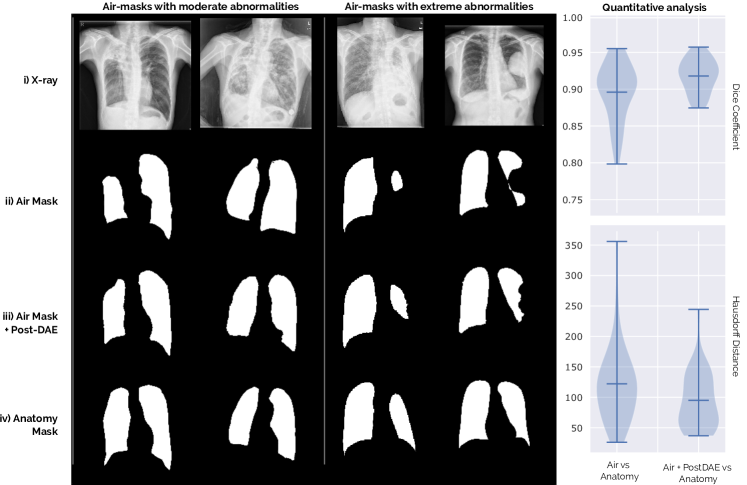

Refer to caption

Figure 5: Analysis for out-of-distribution segmentation masks presenting moderate and extreme abnormalities for tuberculosis patients from the Shenzen database. See Section V-A.A for a complete discussion about this experiment.

The second scenario is related to abnormal cases. Big occlusions or deformed organs, possibly due to manifestations of a particular disease or radiological occlusions, could make these masks look entirely different from the anatomically plausible cases. To analyze the behaviour of our model in this scenario, we employed a different chest X-ray dataset containing patients diagnosed with tuberculosis. This dataset is a subset of the original Shenzhen database [32, 33] formed by 38 X-ray images exhibiting tuberculosis manifestations. Every image was annotated by two expert radiologists following different approaches to delineate the lungs as discussed in [34]. The first approach was to segment only the air cavity part of the lung field, i.e. segmenting only the dark part and ignoring lighter areas covered with fluid. We call these the air masks. In the second approach, the annotator delineated the expected anatomy of the lungs, including occluded areas following a comparative approach by “mirroring” the normal lung field onto the abnormal one [34]. We call these anatomy masks. Figure 5 shows examples for both types of segmentation masks (rows (ii) and (iv)). Note that those corresponding to the air approach might present moderate or extreme abnormalities (e.g. missing complete parts of the lung). We applied the Post-DAE model to the air masks and analyzed its effect.

We used a Post-DAE model trained with the JSRT dataset, where the lung masks are mostly anatomically plausible since there are no big abnormalities or occlusions in the images. As expected, our method tends to map the air to the anatomy masks. However, note that when abnormalities are too extreme (see columns 3 and 4 in Figure 5) the real anatomy can not be completely reconstructed. We quantified this experiment by measuring the Dice coefficient between the air and anatomy masks before and after post-processing the air masks with Post-DAE. The violin plots included in Figure 5 show that the post-processed air masks are significantly closer to the anatomy masks than the original ones, both in terms of Dice and Hausdorff metrics. This constitutes, at the same time, an advantage and a limitation of our approach: Post-DAE will transform the segmentation masks so that they look closer to the anatomically plausible ones used at training. These are important facts that must be considered when designing segmentation workflows which include Post-DAE. The same holds for problems different from anatomical segmentation. In scenarios like brain lesion or tumor segmentation, where shape and topology is not regular, the applicability of Post-DAE may be limited.